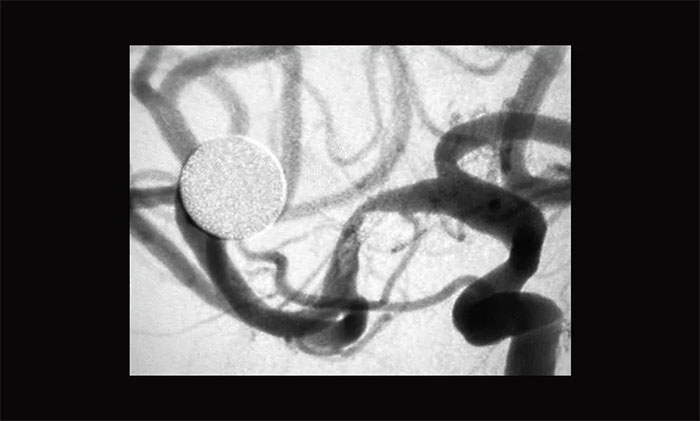

術中,經(jīng)右側(cè)橈動脈穿刺行全腦血管造影可見,右側(cè)大腦中動脈MI段重度狹窄,約90%,遠端血流緩慢,左側(cè)椎動脈起始段迂曲,基底動脈冗擴?紤]患者反復出現(xiàn)腦梗死與右側(cè)大腦中動脈狹窄有關,且其它血管對右側(cè)大腦中動脈供血區(qū)域基本無代償,一旦發(fā)生大腦中動脈閉塞將發(fā)生嚴重后果。遂決定行右側(cè)大腦中動脈M1段球囊擴張術及取栓術。

▲ 術前DSA影像:右側(cè)大腦中動脈MI段重度狹窄